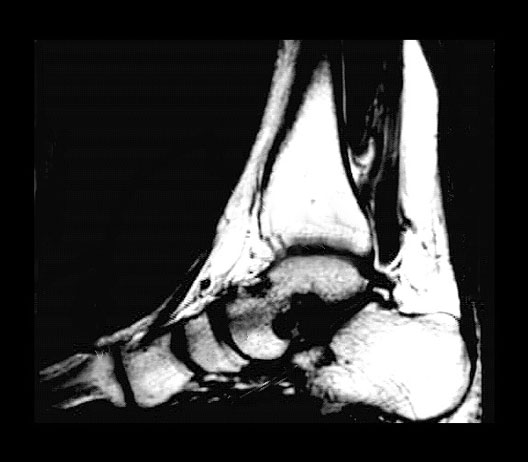

Ankle MRI

1. First metatarsal bone

2. Navicular

3. Talocrural joint (ankle)

4. Lower end of tibia

5. Medial cuneiform

6. Talus

7. Sustentaculum tali

8. Calcaneus

9. Calcaneal tendon